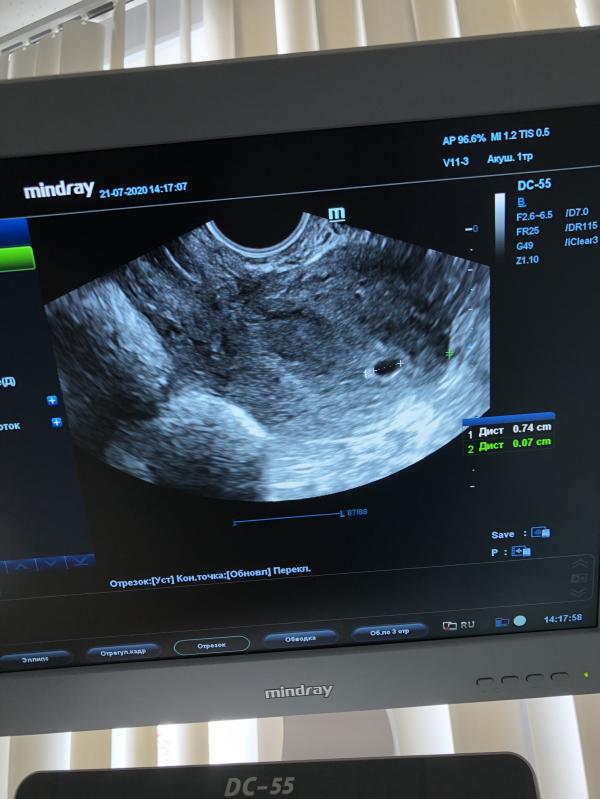

Оказывается у меня отслойка плаценты небольшая слава Богу, есть угроза выкидыша. Назначили дюфастон, папаверин, ношпу, фолиевую и vitrum prenatal, ну и конечно постельный режим

Вот и фото первого узи, срок маленький и эмбрион не видно пока, но я так отрада что там малыш мой растёт❤️